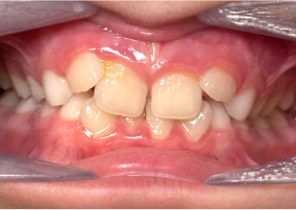

Report sul Caso 2

7 anni 11 mesi 24 fasi di Invisalign® Palatal Expander

Per gentile concessione del Dr. David R. Boschken

Pre espansione Invisalign Palatal Expander

Post espansione Invisalign Palatal Expander

Dopo il trattamento con Invisalign Palatal Expander